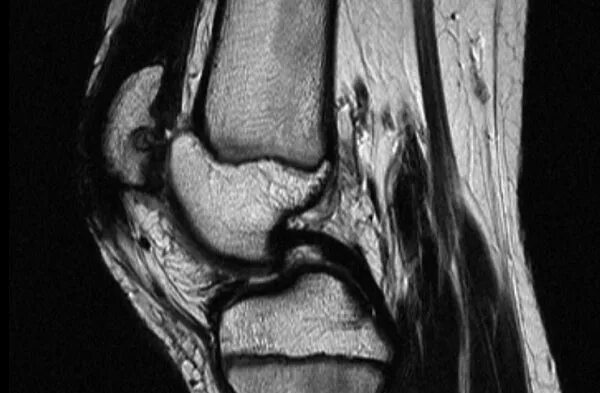

На мрт нужно снимать